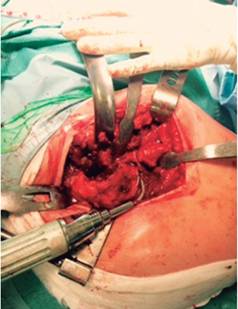

La paciente es intervenida. Se le implanta un acetábulo de titanio poroso (Trilogy® de Zimmer®) fijado con dos tornillos (Figuras 3 y 4). Para minimizar el riesgo de fracturas intraoperatorias, se coloca un cótilo no cementado sin el pressfit habitual de 2 mm (fresando un diámetro de 48 mm e implantando un cótilo de 48 mm). Para el componente femoral, se elige el vástago cónico de Wagner (Wagner Cone Prosthesis® Hip Stem de Zimmer®), que permite un mayor control de la anteversión femoral y minimiza el riesgo de fracturas intraoperatorias (Figura 5).2 Previamente a la inserción del vástago, se coloca un cerclaje profiláctico a nivel del cálcar para minimizar todavía más dicho riesgo (Figura 6).

Figura 3: Luxación quirúrgica de la cadera derecha; se observa la calidad ósea de la cabeza femoral.